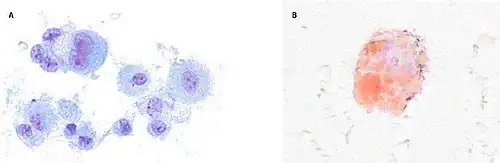

Bronchoalveolar lavage specimens may exhibit an increased level of neutrophils in combination with lymphocytes and vacuole-laden macrophages.[22] Lavage cytology with oil red O staining demonstrated extensive lipid-laden alveolar macrophages.[66][67] In the few cases in which lung biopsies were performed, the results were consistent with acute lung injury and included a broad range of features, such as acute fibrinous pneumonitis, diffuse alveolar damage, lipid-laden macrophages, and organizing pneumonia.[41][62] Lung biopsies often showed neutrophil predominance as well, with rare eosinophils.[64]